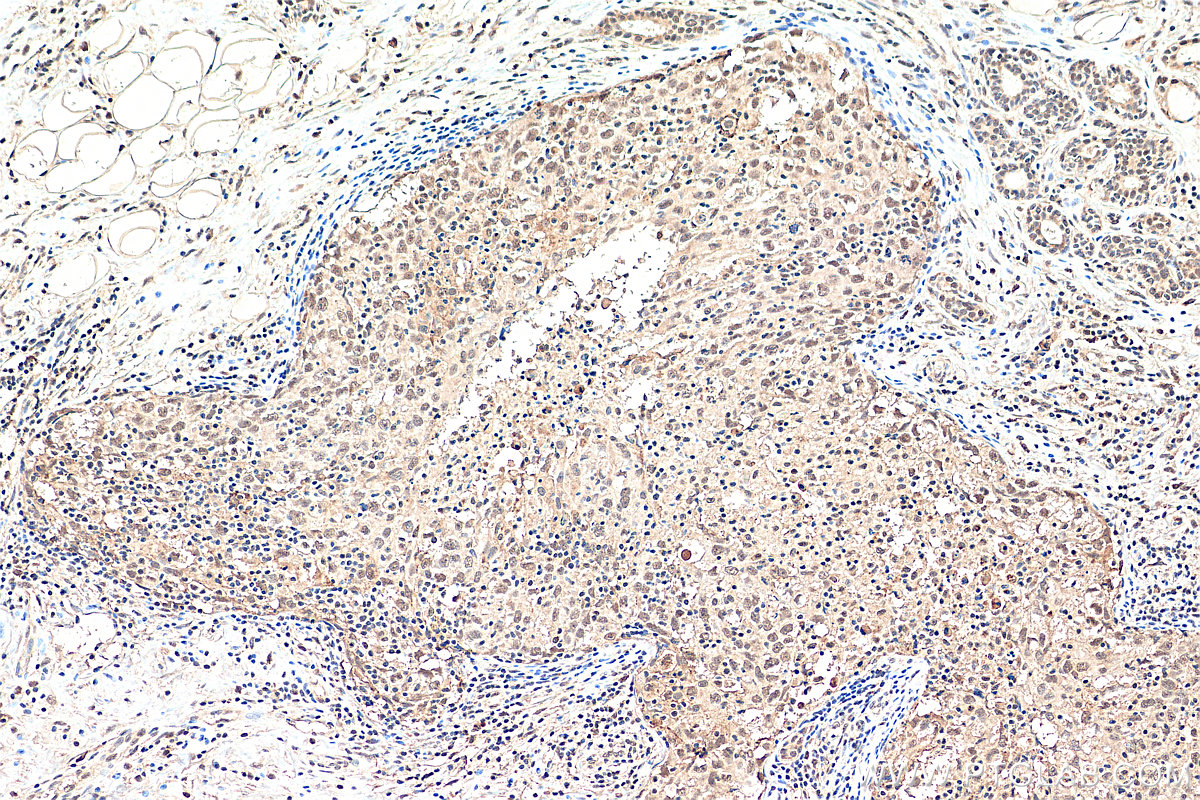

| Positive IHC detected in | human breast cancer tissue Note: suggested antigen retrieval with TE buffer pH 9.0; (*) Alternatively, antigen retrieval may be performed with citrate buffer pH 6.0 |

| Immunohistochemistry (IHC) | IHC : 1:50-1:500 |